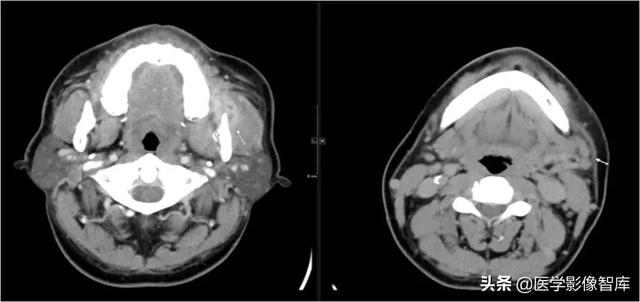

翼颌间隙、咽旁间隙

左下阻生齿拔除术后10天,伴吞咽疼痛4天。

手术导致的翼颌间隙及咽旁间隙脓肿形成。